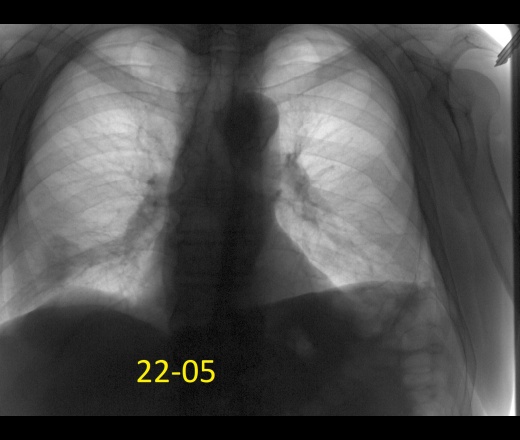

Мужчина 60лет. Диагностическая флюорография, 22 мая был поставлен диагноз пневмония с\д справа, пришел к нам на контроль второй раз.  Думаю все хорошо можно отпускать? Ваше мнение коллеги?

Да, динамика положительная, 4 сегмент с гиповентиляцией. Ограничился бы рентген контролем ч\з 1-1.5 мес.

Слева над диафрагмой дисковидный ателектаз?

Да нет, купол диафрагмы. (с учетом 22.05, 06.06.)

По всей видимости плеврит перенесен...

Погодите благодарить. Неспокойная картина, так думаю.

Динамика положительная. Слева облитерация костодиафрагмального синуса вследствии перенесенного плеврита